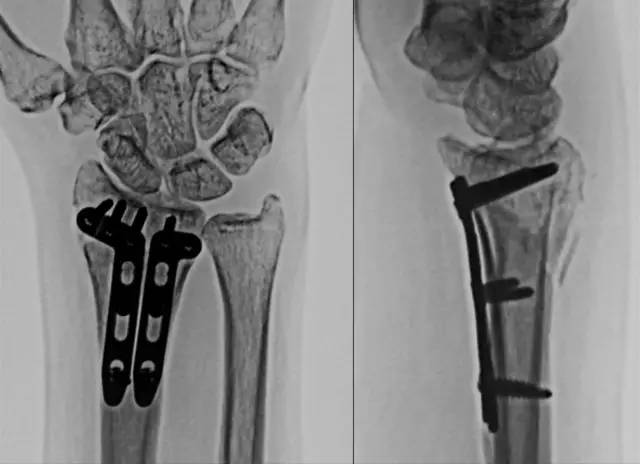

在桡腕关节中插入一枚克氏针,这有助于确定桡骨最远端的界限。如果存在关节边缘的小骨折块,可将掌侧 2.4 mm 钢板放置在桡骨远端关节边缘进行固定。换句话说,月骨关节面的小骨折块可用 2.4 mm「L」或「T」型钢板进行支撑,如图 2。

图 2. 复杂的掌侧关节内骨折,应用两块「L」型钢板进行支撑